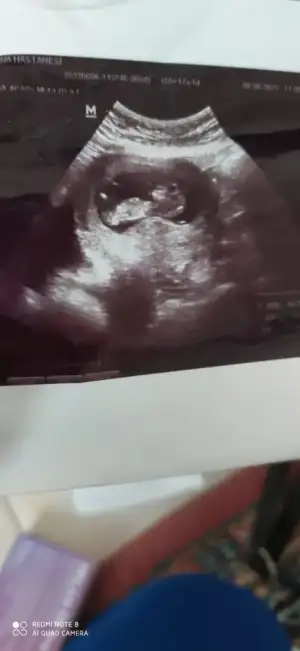

Yorumlar mısınız benımde karından 8 haftalık

• IMG-20220628-WA0001.webp

IMG-20220628-WA0001.webp

14,9 KB · Görüntüleme: 87